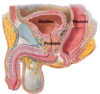

Male Pelvic Viscera Flashcards

Label all:

Label all:

Label all: